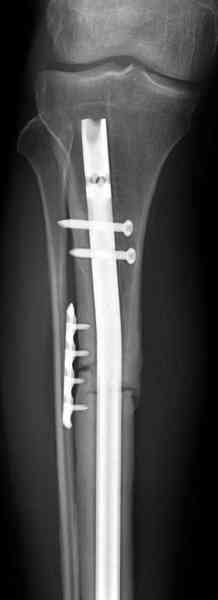

Недавно на нашей ежемесячной Morbidity&Mortality

conference мы разбирали похожий случай, ложный сустав большеберцовой кости после резекции опухоли.

Оперирован в военном госпитале с заменой сегмента

аллокостью большеберцовой кости и после демобилизации явился для постоянного наблюдения по месту жительства.

Наши имели проблему со сращением, пришлось им сделать динамизацию, дополнительную аутопластику.

Снимки представлены.